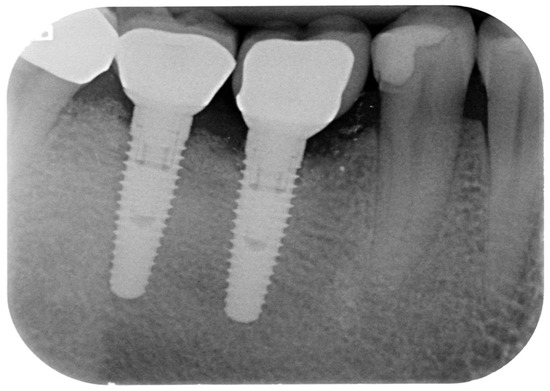

2. Materials and Methods

3. Results

| PD | 8.14 ± 1.156 | 8 ± 1 | 7.7, 8.6 | 3.72 ± 0.649 | 4 ± 4 | 3.5, 4 | 4.14 ± 1.093 | 4 ± 4 | 3.7, 4.5 | p < 0.0005 |